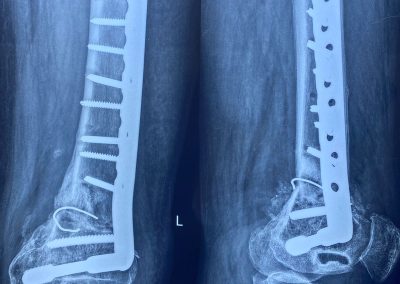

صورة اشعة تبين شريحة تم تركيبها بشكل خاطئ ترتب عليها اعوجاج بالركبة

الأشعات بعد الجراحة مباشرة و الاشعات الاخيره بعد الجراحة ب ٦ أشهر